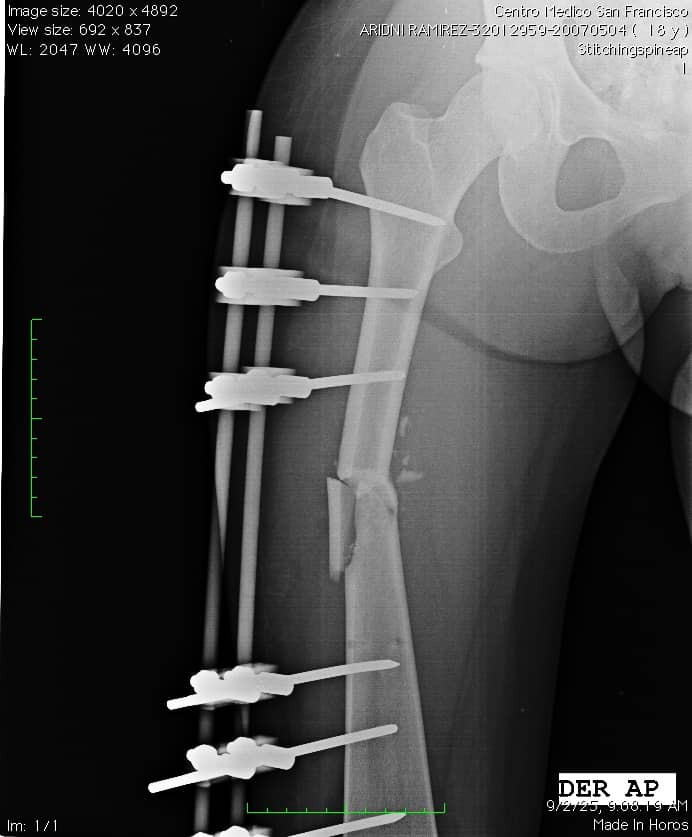

Hace poco, Aridni sufrió un grave accidente que le dejó múltiples lesiones: fractura grave de mandíbula, doble fractura de fémur, lesiones en el brazo y otras complicaciones que requieren atención médica urgente. Actualmente se encuentra en Venezuela, donde lamentablemente la salud pública atraviesa una crisis muy profunda. No hay insumos, quirófanos funcionales ni condiciones mínimas para que pueda ser operada en un hospital público.

La única opción viable es trasladarla a una clínica u hospital privado donde pueda recibir las cirugías que necesita para salvar su pierna, su mandíbula y su movilidad. Pero estos costos son altísimos. Yo soy su hermana mayor, la única de la familia que está fuera del país, y aunque hago todo lo posible por cubrir sus gastos, la situación me sobrepasa.